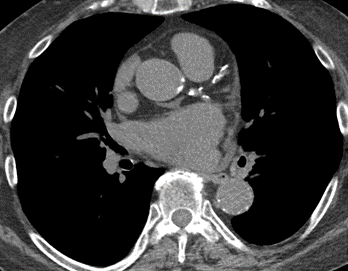

Coronary artery calcification

Coronary artery calcification can be identified as high-attenuation material in the path of a coronary artery. For non-gated thoracic CT in routine clinical practice, it is recommended to use a simple visual ordinal score performed on a whole-patient basis. CAC is scored as absent, mild, moderate, or severe on a whole-patient basis to summarize the cumulative findings in all the coronary arteries. This approach can be applied to both non-contrast and contrast-enhanced images.

Valvular calcification

Valvular calcification can be identified as high-attenuation material in the region of the aortic valve. Care should be taken to differentiate valve calcification from calcification in the aortic root, mitral annulus, or coronary arteries (aortic valve).